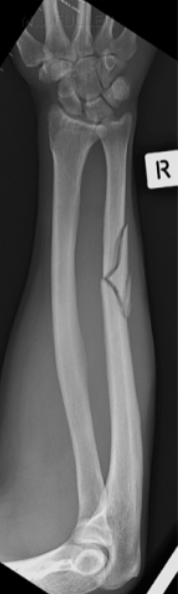

Oblique Fractures

Fracture line is

oblique to the

longitudinal axis

of the bone